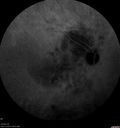

63 year old female She noticed a new thumbprint on her right eye with decreased vision March 10, 2019.  She waited a few days.  She was an eye institute where they said it was a cataract and scheduled for surgery.  She asked why if the cataracts are the same there was trouble with the one eye. He agreed and sent her to his retina specialist who noticed a problem and suggested a referral out. She has no health problems otherwise but has not been to a doctor lately.   VA OD: Dcc20/125 PHNI Ncc20/400 VA OS: Dcc20/50 PH20/32 NccJ5 IOP: TP: OD:23 OS:22 Time:15:56

Lung Cancer Metastasis to Right Eye372 views63 year old female with vision loss for 6 weeks. She had been scheduled for cataract surgery and then a tumor was found. She was ultimately diagnosed with lung cancer. Vision is 20/10000000

lung-jetop-092019.png

Metastatic Non Small Cell Lung Cancer to Choroid - After External radiation603 views00000